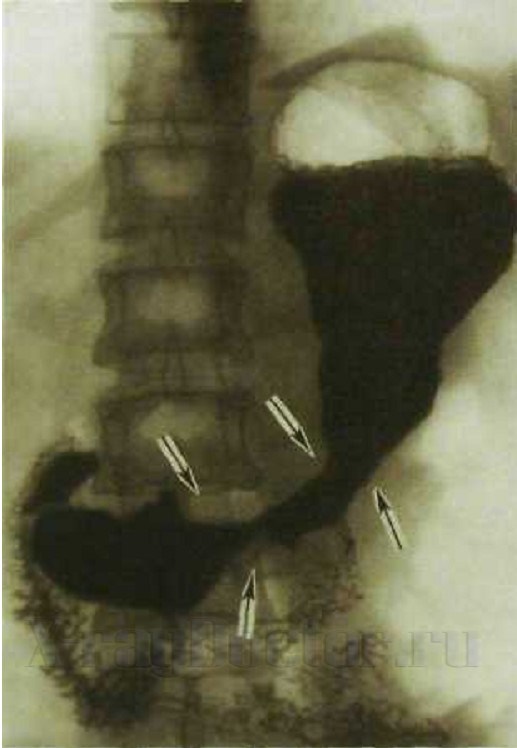

Рентгенологи медицинских поликлиник проводят чаще всего классическое исследование. При нем вначале выполняется просвечивание желудка в вертикальном положении пациента. После принятия пациентом глотка контраста под контролем рентген-телевизионного монитора изучается состояние складок и врач делает снимки важных анатомических образований. Равномерное распределение контраста проводится с помощью дозированной компрессии. Для этого оборудование оснащено специальными тубусами.

На следующем этапе пациент выпивает целый стакан контраста (около 200 мл), что приводит к тугому наполнению. Исследование позволяет выявить патологию внешнего контура тонкой кишки при раковых и язвенных дефектах.

На прицельных снимках при классическом исследовании должны быть отражены следующие анатомические образования: